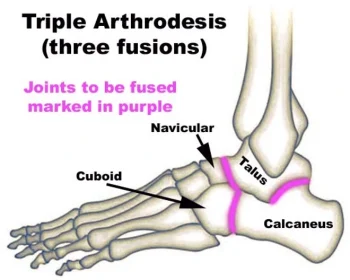

Triple arthrodesis fuses three foot joints to enhance stability and relieve pain from severe conditions.